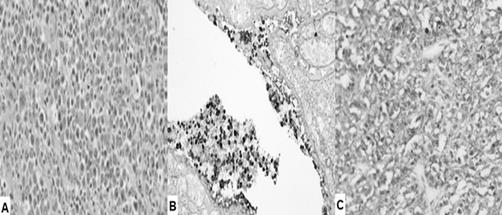

La histopatología mostró una infiltración difusa del parénquima vulvar por células plasmáticas atípicas, caracterizadas por núcleos excéntricos, escaso pleomorfismo y presencia de células binucleadas con nucléolos prominentes. Se observó además una marcada eosinofilia. La inmunohistoquímica demostró positividad para CD138, CD56 y CD79a, y negatividad para CD20 y CD19 (figura 3). Además, se observó restricción ligera de cadena λ. Los hallazgos fueron compatibles con PEM vulvar.

Figura 3 Imágenes de histopatología del plasmocitoma extramedular de vulva. A) Infiltrado difuso de células inflamatorias y plasmáticas atípicas bien diferenciadas con núcleos excéntricos y ligero polimorfismo nuclear (Coloración hematoxilina-eosina, 100X. B) Inmunohistoquímica que muestra células neoplásicas con tinción positiva a CD56. C) Células neoplásicas que muestran positividad difusa a la tinción CD138.